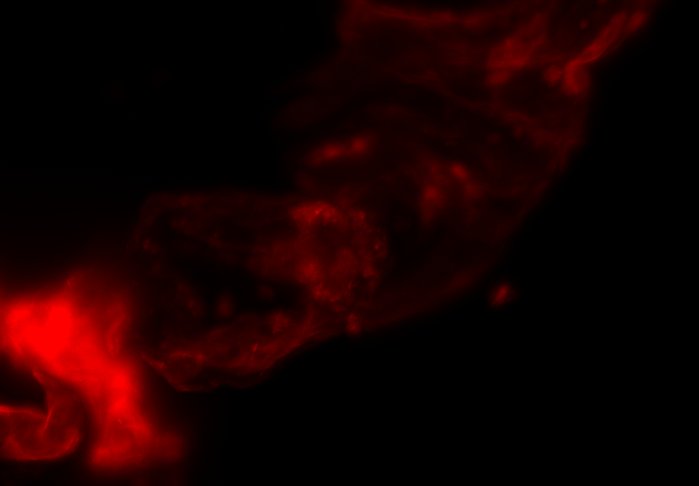

The combination of prospective optical gating for real-time phase matching and prospective optical gating for long-term phase locking allow us to capture in phase images over extended periods of times. Figure 4 demonstrates this phase locking over 18+ hours across a key developmental phase - heart looping.

We have previously shown the use of prospective optical gating with SPIM for the capture of 3D fluorescence data of the living, beating zebrafish heart. However, until now it was not possible to maintain synchronisation over timescales of an hour or more, due to changes in the appearance of the heart. Here we have demonstrated the successful application of combining prospective and retrospective optical gating techniques in order to update the reference heartbeat and phase lock between old and new references.

We have described how a combination of drift correction, inter-frame correlation and least squares regression can be used to accurately and robustly update the reference heartbeat and target frame. We have shown that this allows for phase locked imaging over developmental time scales. In particular we have demonstrated the ability to maintain synchronisation over 18+ hours around the heart looping stage of cardiac development in zebrafish.